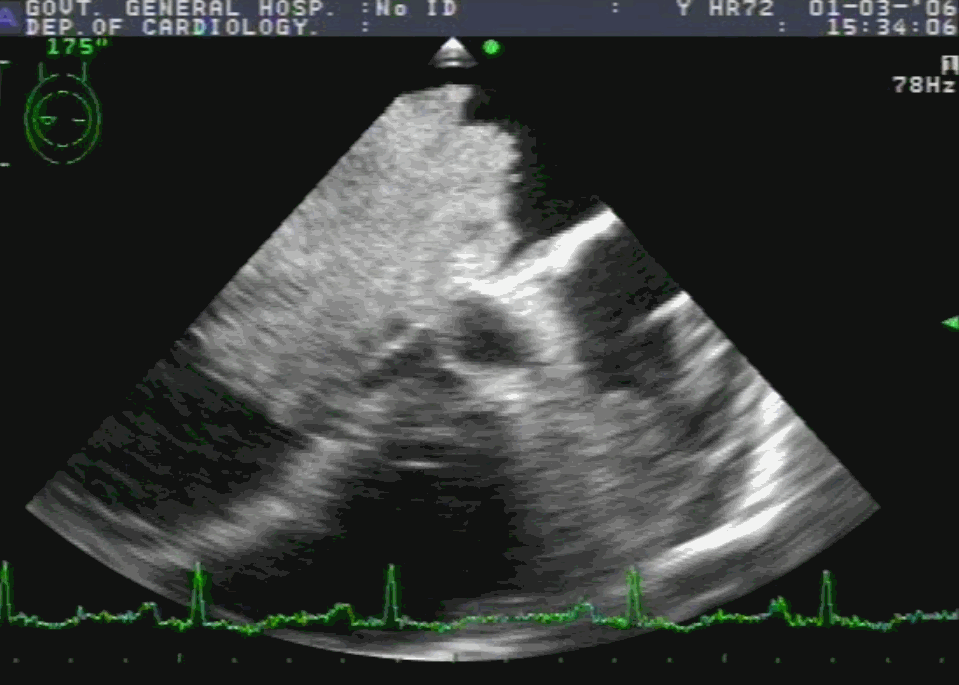

Bicaval view is an Important TEE view to visualize, the LA, IAS, and right atrium. I used to have some trouble getting oriented to this view. Hence this post. It is obtained in the 90-120 degree view at the mid esophageal position. Imagine the patient is lying on his left side and the probe comes from above down between the spine and heart to the LA from within the esophagus. This is the best view to see IAS in the profile.(Subcostal TTE can also do it) Note how the LA hugs the right atrium which is actually an ill-defined (In TEE I mean) common meeting point of both IVC and SVC. Also important is the relationship of RUPV with SVC & the horizontally running RPA sitting right over the top of LA.

The relationship between RUPV and SVC is crucial in device closure of large ASD, especially in sinus venous defect.

Clinical Importance of this view

Very useful in ASD rim morphology especially in the posterosuperior rim.

Delineates clearly the defect boundaries in SVC ASD.

This view doesn’t miss even the smallest PFO (With Contrast )

Can be used to guide IAS puncture in structural heart Interventions.

IVC /SVC mass extension into RA well visualized.